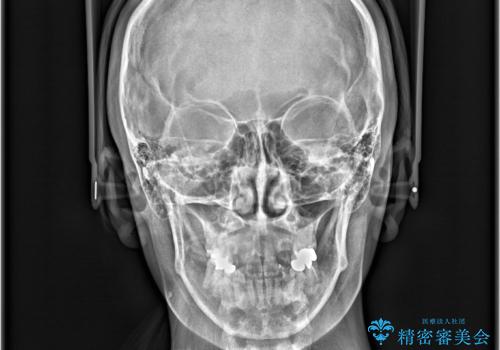

- 開咬と歯のデコボコ(叢生)、八重歯を主訴にご来院された患者様です。

矯正の精密検査の結果、上顎左右4番および下顎左右5番の計4本を抜歯し、ワイヤー矯正(クリア装置)にて治療を行いました。